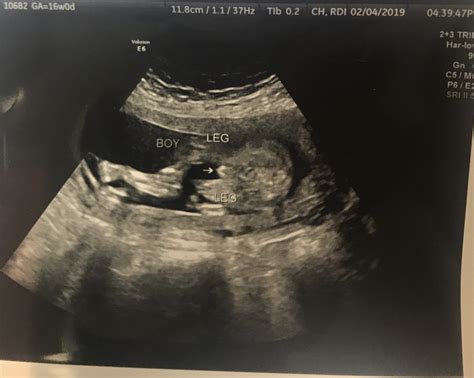

· The 16-weekultrasound is often your first serious glimpse at your baby. Here's what you can expect. · As usual, you’ll likely have a urine test; your OB will be checking your urine for signs of gestational diabetes and preeclampsia. You may also have a 16 weeks pregnant ultrasound at your appointment, but don’t be alarmed if you don’t, as your OB will do one closer to mid-pregnancy. View all At a 16-week pregnancy scan, you’ll see your baby’s development and check for any potential issues, ensuring a healthy pregnancy journey. A 16-week pregnancy scan, also known as a mid-pregnancy ultrasound or anomaly scan, is an essential part of prenatal care. Find out what to expect from your 16-weekultrasound during your pregnancy, including the development of your baby and what the scan can reveal. What to expect while getting ready for a 16 weekultrasound? Read a complete guide to learn about the purpose and procedure, and prepare for what you will see. · Ultrasounds help track your baby's growth and spot any issues early. Most people have a few key ultrasounds, but certain conditions may require more. Safety is a top priority, so ultrasounds... Is a 16-weekultrasound typical? Understand the standard prenatal scan schedule, specific reasons for an early check, and what can be assessed at this stage. · As usual, you’ll likely have a urine test; your OB will be checking your urine for signs of gestational diabetes and preeclampsia. You may also have a 16 weeks pregnant ultrasound at your appointment, but don’t be alarmed if you don’t, as your OB will do one closer to mid-pregnancy. At a 16-week pregnancy scan, you’ll see your baby’s development and check for any potential issues, ensuring a healthy pregnancy journey. A 16-week pregnancy scan, also known as a mid-pregnancy ultrasound or anomaly scan, is an essential part of prenatal care. Find out what to expect from your 16-weekultrasound during your pregnancy, including the development of your baby and what the scan can reveal. What to expect while getting ready for a 16 weekultrasound? Read a complete guide to learn about the purpose and procedure, and prepare for what you will see. · Ultrasounds help track your baby's growth and spot any issues early. Most people have a few key ultrasounds, but certain conditions may require more. Safety is a top priority, so ultrasounds... Is a 16-weekultrasound typical? Understand the standard prenatal scan schedule, specific reasons for an early check, and what can be assessed at this stage. Discover what to expect during a 16-weekultrasound scan. Learn about baby development and gender determination at this exciting stage of pregnancy. • What are ultrasounds in pregnancy?• Why do I need a 16-weekultrasound?• What does a 16-weekultrasound look like? 16Weeks What to Expect | 16weekUltrasound. Diana In The Pink. 698K views • 4 years ago. 16Weeks Pregnant Ultrasound - Baby Gender Reveal.16weekultrasound | 17 weeks pregnant ultrasound, Ultrasound prank, Ultrasound pictures. Discover what happens during the 16-weekultrasound, how your baby is developing, and why this scan is an important milestone in pregnancy care. At week 16 your belly will be growing pretty fast. During The 16WeekUltrasound. This ultrasound will be carried out the same way as your first. Pregnancy work-up included a traditional 22-weekultrasound scan, an echocardiography, and the option of a 10-gene Rasopathy panel after a normal 16-week scan. Why Should Pregnant Women Have an Ultrasound at 16Week? Things start to get a bit exciting once you hit the 16-week mark and ultrasound is important to understand your baby’s progress.